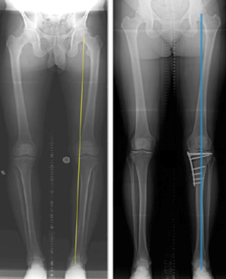

The X-rays below show medial compartment arthritis. Planning X-rays before the HTO show the body weight passing though the medial (inner) arthritic compartment (yellow line). After the HTO the body weight passes through the lateral (outer) normal compartment (blue line).